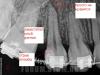

IRGL Опубликовано 15 апреля, 2011 Поделиться Опубликовано 15 апреля, 2011 неа ставлю на 2 отдельных канали и возможно корня))) там верхушки фигу показывают. кривулины http://funportal.info/smiles/smile287.gifа разборка мне видится как то так: http://s43.radikal.ru/i100/1104/96/a080cab7d1bf.jpg Ссылка на комментарий

zybnaya feya Опубликовано 15 апреля, 2011 Поделиться Опубликовано 15 апреля, 2011 (изменено) там верхушки фигу показывают. кривулины http://funportal.info/smiles/smile287.gifа разборка мне видится как то так: кто туда влезет,тому и дуля хоршо что не мне вижу контуры также,но кмк 2 там корняhttp://s12.radikal.ru/i185/1104/7b/911f93e5d6d3.jpg Изменено 15 апреля, 2011 пользователем zybnaya feya Ссылка на комментарий

Ico Опубликовано 15 апреля, 2011 Поделиться Опубликовано 15 апреля, 2011 кто туда влезет,тому и дуля хоршо что не мне вижу контуры также,но кмк 2 там корняhttp://s12.radikal.ru/i185/1104/7b/911f93e5d6d3.jpghttp://s016.radikal.ru/i334/1104/59/9d7f354a51d5.jpgПЛЮС АДЫН) Ссылка на комментарий

DokDent Опубликовано 15 апреля, 2011 Поделиться Опубликовано 15 апреля, 2011 'Ico' date='15.4.2011, 18:00' post='231852'] http://s016.radikal.ru/i337/1104/65/ec5bfb2b2ea3.jpg А это не трещина? Ссылка на комментарий

BORA Опубликовано 15 апреля, 2011 Автор Поделиться Опубликовано 15 апреля, 2011 'Ico' date='15.4.2011, 18:00' post='231852'] http://s016.radikal.ru/i337/1104/65/ec5bfb2b2ea3.jpg А это не трещина? так так...слушайте а действительно похоже...нельзя исключать,если учесть конфигурацию апексов и тягу... Ссылка на комментарий

zybnaya feya Опубликовано 15 апреля, 2011 Поделиться Опубликовано 15 апреля, 2011 (изменено) Это рисунок кости,кмк Изменено 15 апреля, 2011 пользователем zybnaya feya Ссылка на комментарий